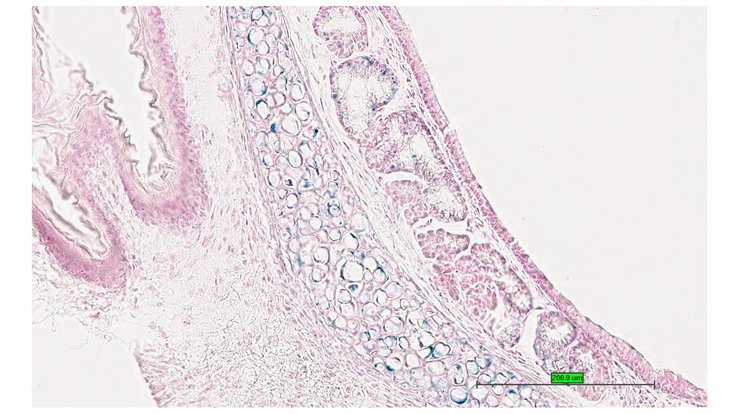

TS28: duodenum Present UC Davis_1884597

Specimen UC Davis_1884598: postnatal adult; Bcs1ltm1.1(KOMP)Vlcg/Bcs1l+ (more )

TS28: jejunum Present UC Davis_1884598

Specimen UC Davis_1884599: postnatal adult; Bcs1ltm1.1(KOMP)Vlcg/Bcs1l+ (more )

TS28: ileum Present UC Davis_1884599

TS28: jejunum Present UC Davis_1884643

Specimen UC Davis_1884644: postnatal adult; Bcs1ltm1.1(KOMP)Vlcg/Bcs1l+ (more )

TS28: ileum Present UC Davis_1884644